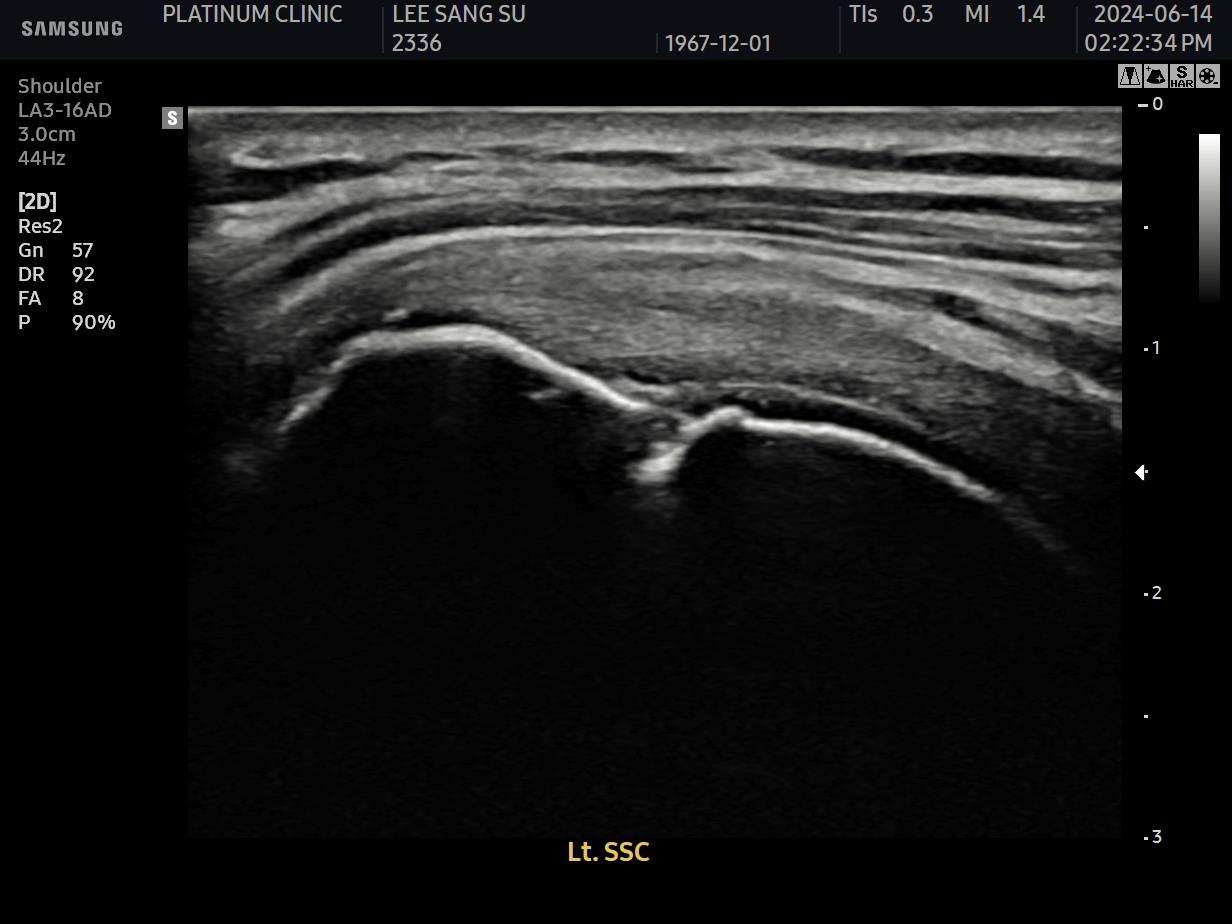

초음파 검사로 확인할 수 있습니다.

치료 전 초음파에서 검게 보이던 파열 부위가, 치료 후에는 정상 인대처럼 하얗게 보입니다. 이것이 구조적 회복의 증거입니다.

안 아파요"라는 주관적 느낌만으로 치료 완료를 판단하면 안 됩니다. 영상으로 확인된 구조적 회복이 있어야 진정한 치료입니다.

초음파 검사에서 손상 부위가 회복되었음이 확인되어야 합니다.

파열 부위가 재생되어 정상 에코(밝기)를 보임

인대 두께가 정상 범위로 회복됨

주변 염증 소견이 사라짐

초음파 결과:

이전에 검게 보이던 파열 부위가 하얗게 재생됨

주변 염증 소견 소실